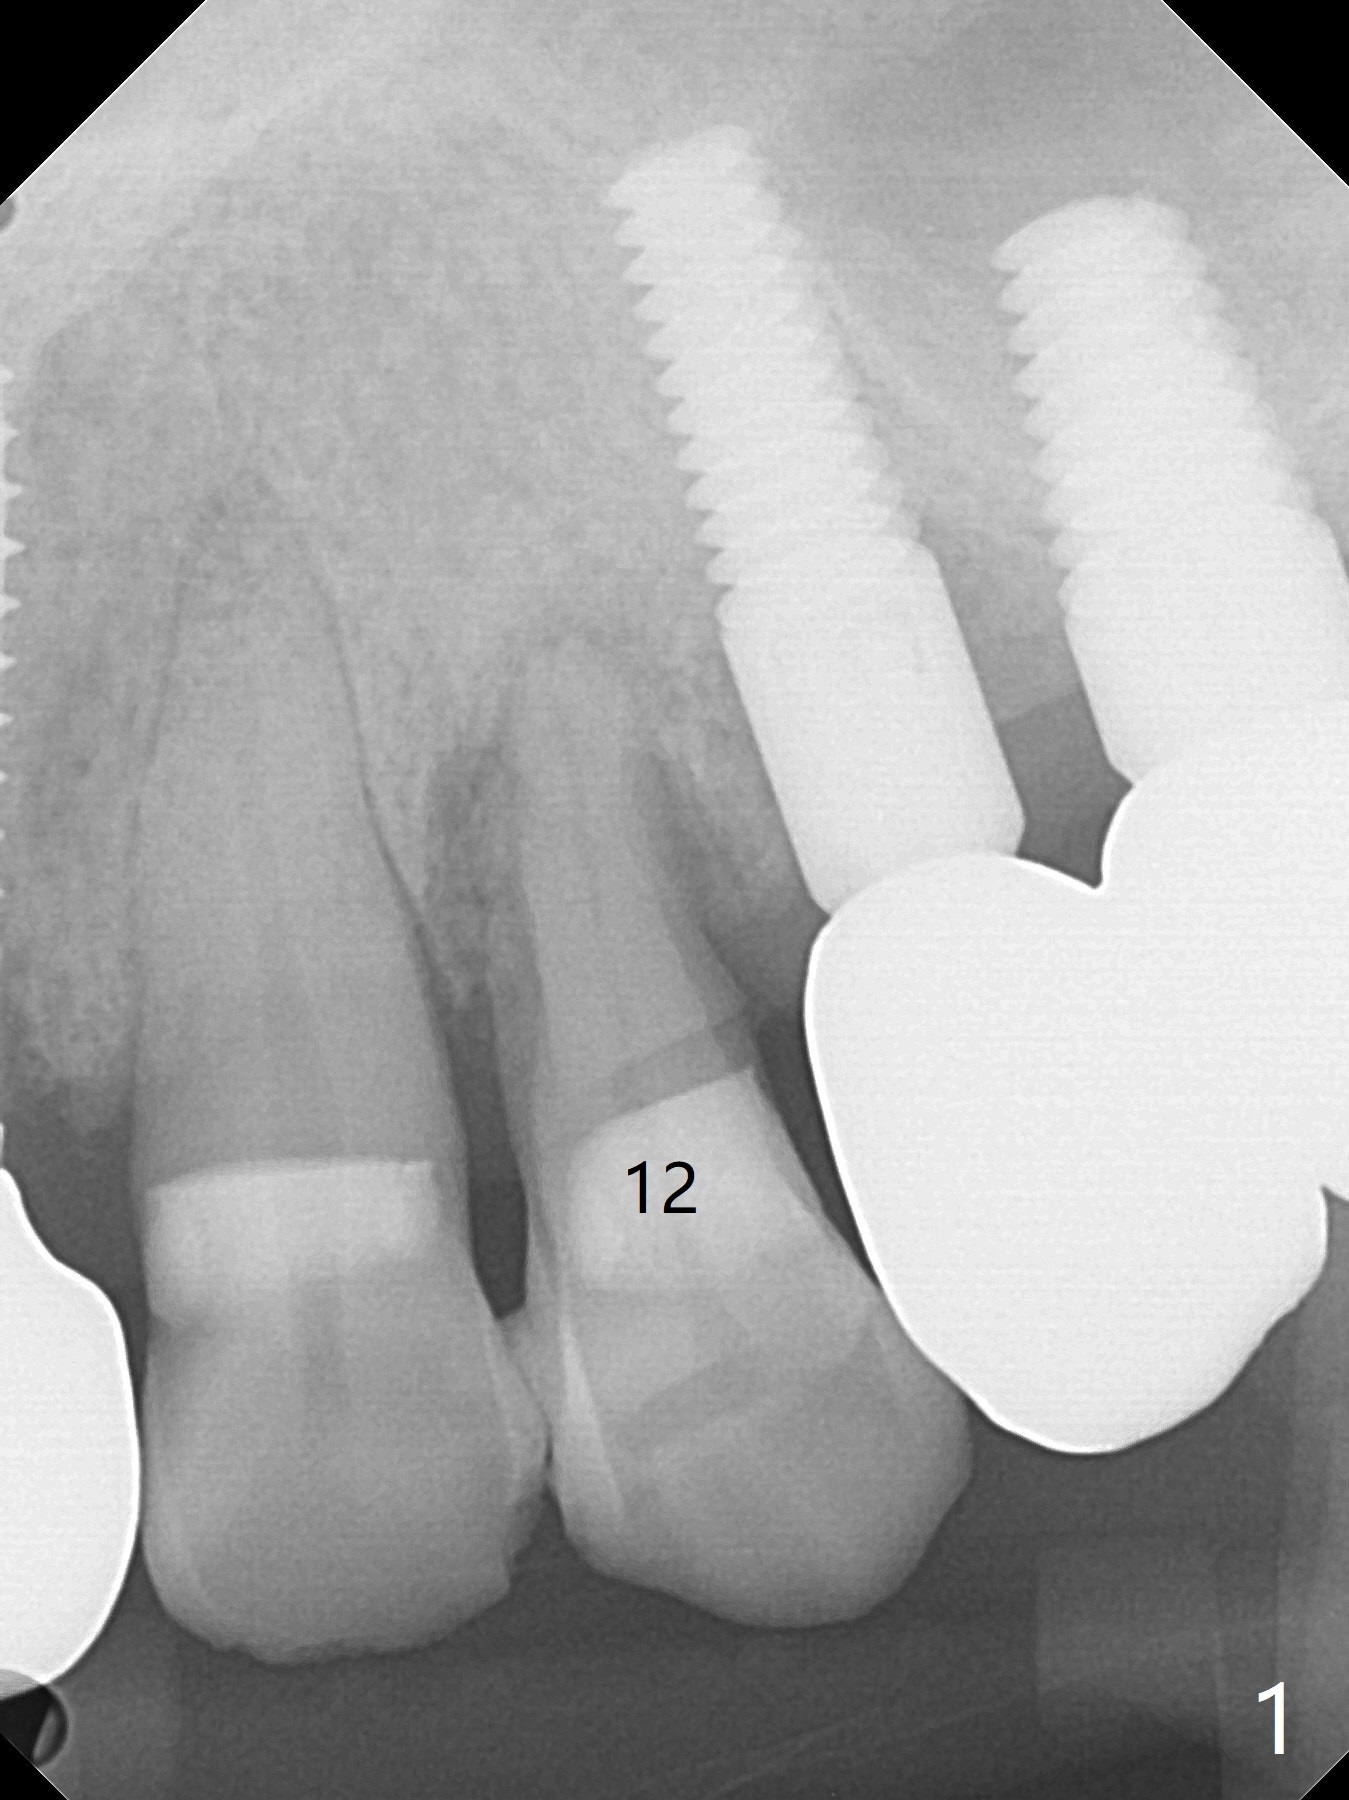

A 66-year-old man agrees to extract #12 for implant immediate post #10 implant crown cementation (Fig.1). Because of the narrow mesiodistal space, either a 1-piece (Fig.2) or 3.5 mm 2-piece (Fig.3) implant will be placed.